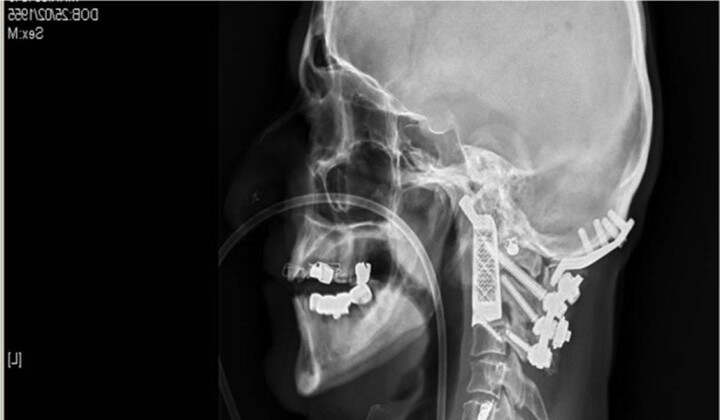

現(xiàn)今,又一科學(xué)奇跡發(fā)生,來(lái)自澳大利亞悉尼威爾斯親王醫(yī)院的醫(yī)生莫布斯,利用3D打印技術(shù)做出了兩塊椎骨的替代品。完成了號(hào)稱“世界第一”外科手術(shù):醫(yī)生植入3D打印椎體。

患者是一個(gè)60歲的老人,飽受脊索瘤的折磨,脊索瘤在癌癥里也是一個(gè)頑癥。在他脖子上的兩個(gè)椎體,不斷長(zhǎng)大,并不斷收緊威脅病人的脊髓。好在3D技術(shù)的發(fā)展,讓醫(yī)生能夠植入兩個(gè)新的椎骨。

莫布斯與澳大利亞醫(yī)療設(shè)備制造商Anatomics合作,通過(guò)3D打印完美的制作出病人前兩塊椎骨的復(fù)制品出鈦。這是第一次,這兩種特定頸骨被打印出并植入患者體內(nèi)?!澳玫竭@個(gè)能夠打印的植入物,你就知道這是一次多完美的配合,因?yàn)槟阋呀?jīng)做好了一個(gè)模型,剩下的只用享受喜悅就好了”,莫布斯告訴搭檔Anatomics.“這就像有人第一次點(diǎn)亮燈泡說(shuō),天哪,這要不是未來(lái),我不知道還有什么是”。

手術(shù)本身就是個(gè)不小的壯舉。15小時(shí)的過(guò)程充滿了危險(xiǎn),手術(shù)要在脊髓頂部以及腦干和許多重大動(dòng)脈相近的范圍內(nèi)操作?!拔覀兘裉煺谧龅倪@個(gè)手術(shù)是一個(gè)特別復(fù)雜,漫長(zhǎng)和艱難的手術(shù)。它涉及在其中頸部和頭部連接處操作”,莫布斯說(shuō),“這基本上是從他的脖子切開病人的頭部,將腫瘤取出,將新的椎骨植入,并重新將他的脖子跟后腦勺連接?!敝档脩c幸的是,手術(shù)是成功的。莫布斯能夠切除腫瘤和植入假體。